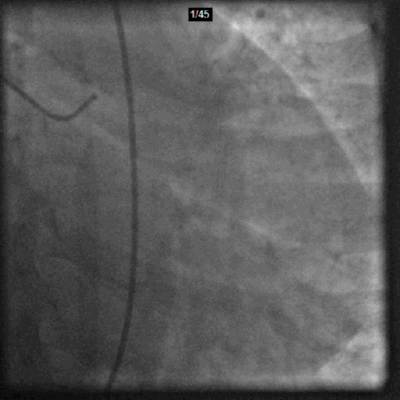

Ultra-low Contrast Angiography-RCA

RCA 2.4mL